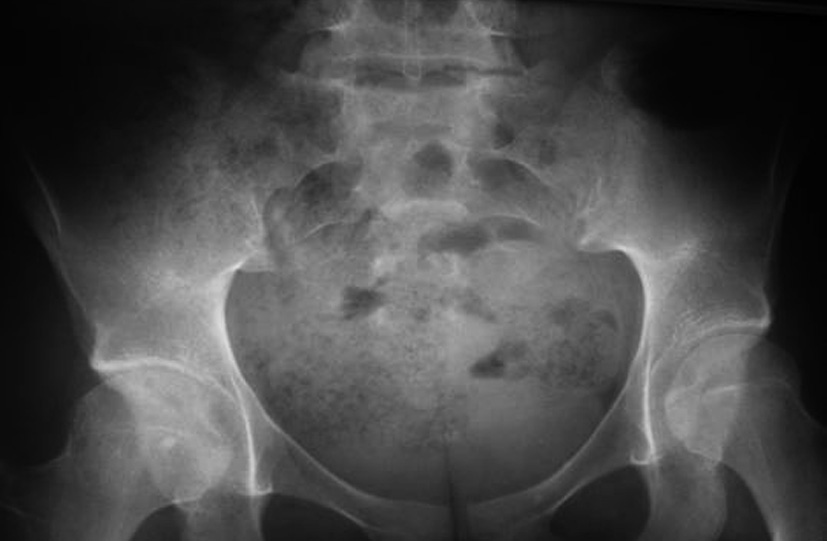

Ces recherches sont négatives. Vous revoyez le patient avec les résultats de clichés radiographiques (rachis thoracique et lombaire face et profil, bassin de face — ce dernier étant sur le cliché joint). Les résultats des examens de laboratoire sont les suivants :